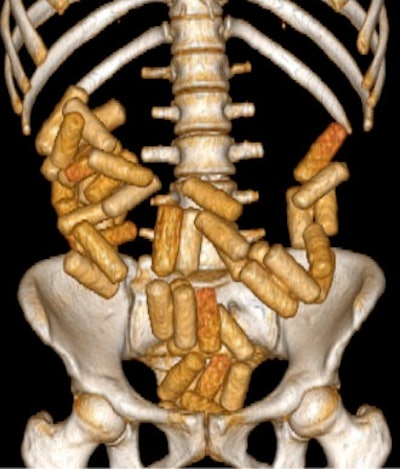

This 3D volume-rendering technique CT image shows numerous large packets of narcotics concealed in a body packer. In a single transport, a body packer can carry 50 to100 packages, each containing 8 g to10 g of narcotic agents, this weighing up to 1 kg in total. Image courtesy of Dr. Mesut Bulakçı."The detection of many drug mule cases through physical examination or laboratory analysis is difficult. The suspect may also provide false information. Therefore, radiological detection and follow-up play a vital role," lead author Dr. Mesut Bulakçı, radiologist at Istanbul Faculty of Medicine, said in an interview with AuntMinnieEurope.com. "The first medical examination is often performed by the doctor at airports or borders and usually with plain film. After this, the suspects are brought to specialized hospitals like ours for detailed examination."